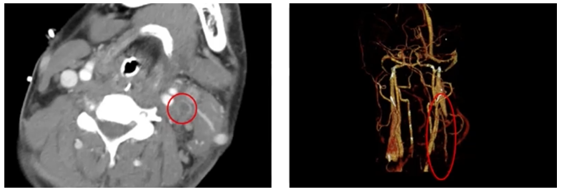

图1 患者胸部CT

图4 患者治疗过程